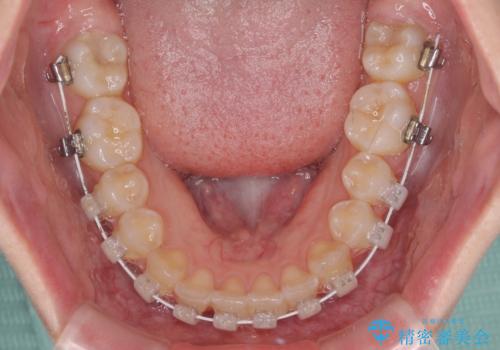

- 審美装置

- 1年2ヶ月

- 10-30回

左右ともに上顎第二大臼歯が外側に転位しており、大変磨きにくくなっているため、補助装置により内側に引き込むことで改善することとしました。

外側を向いていた奥歯は比較的早い時期に歯列に収まり、咬み合わせも磨きやすさも改善することができました。